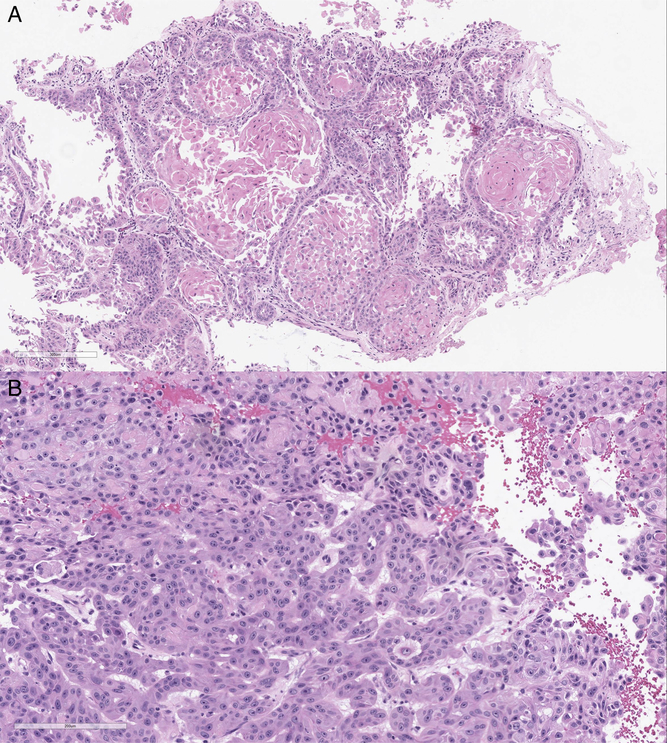

Histopathological examination of the surgical specimen revealed collections of squamoid cells exhibiting mitotic activity, cellular atypia, prominent nucleoli, and keratinization (Figure 3). While the site of origin of SCCs cannot be resolved by morphologic or immunohistochemical analysis, given the presenting clinical picture and the absence of other tumors from previous screening, this most likely represented a metastasis from the cutaneous origin.

Figure 3: Histopathological examinations showing low power (A) and high power (B) views of an epithelial neoplasm supportive of a metastatic squamous cell carcinoma with atypia, prominent nucleoli, and mitotic activity. The cohesive tumor cells form round islands with a central area of keratinization and a surrounding desmoplastic stromal reaction.